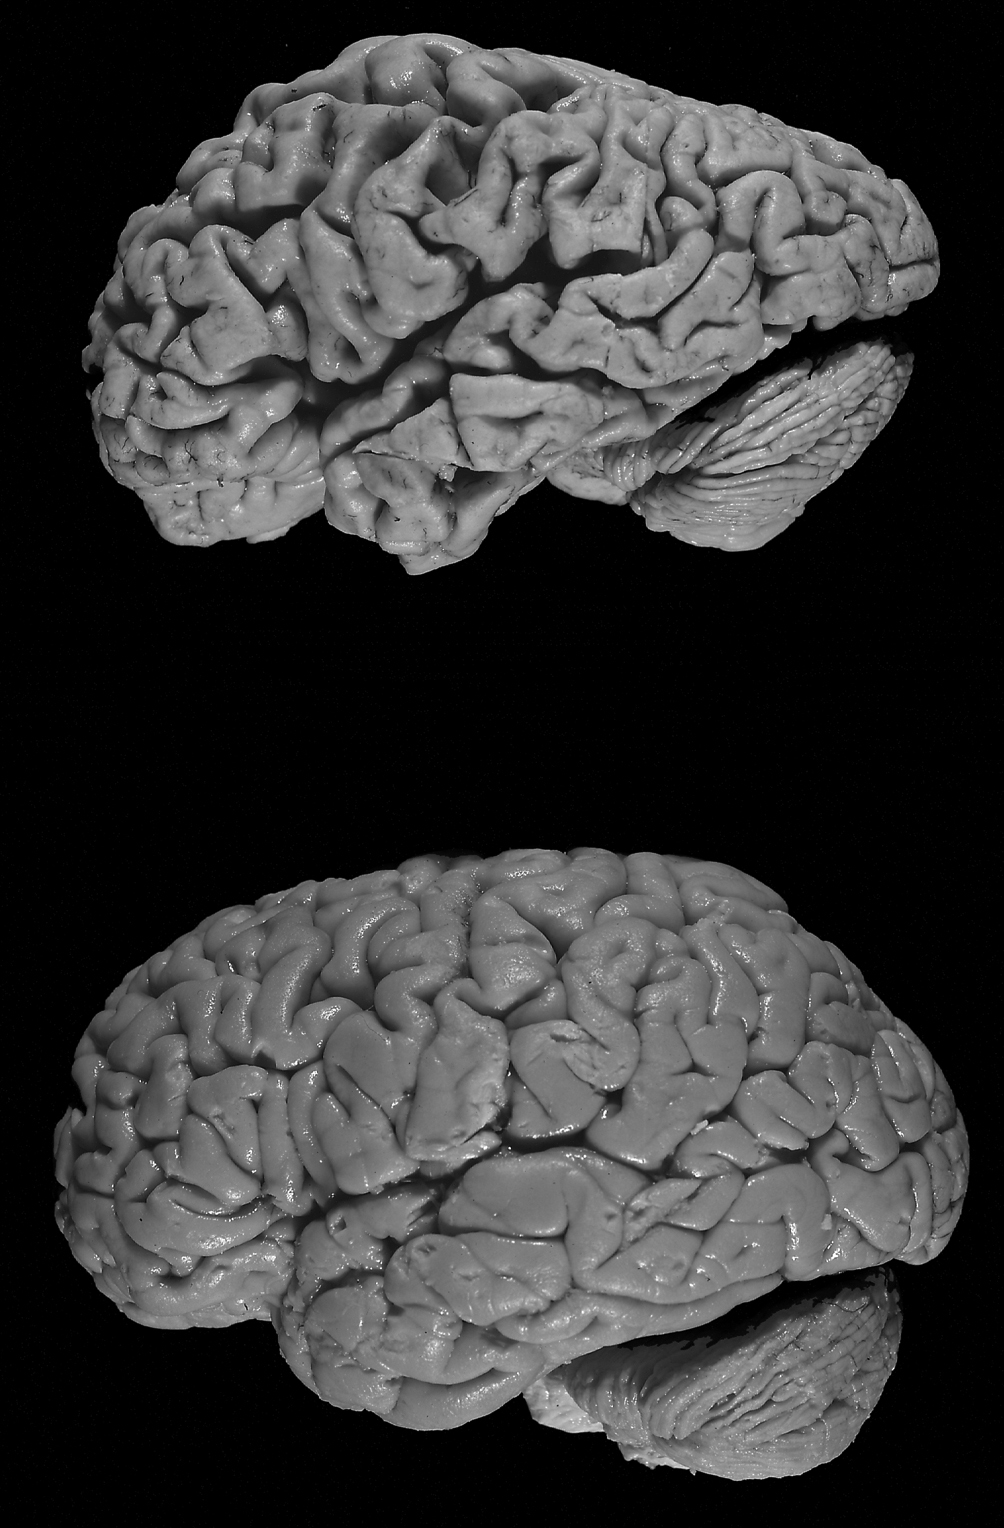

Edwards argued that the case of Mrs. D shows the mind or soul does not exist separately from the brain. When the brain is damaged, the person’s mind is damaged. Mrs. D was kind when her brain was functioning, but her personality disappeared when her brain ceased to function properly, proving that the brain creates the mind.

If the mind were dependent on parts of the brain for existence, it is hard to see how a whole person—a person who can make connections between this memory and that, a person who can calmly and rationally interact with others and perform coherent actions—could return. If parts of the brain were so badly affected by the disease, one would expect only a fragmented individual to remain.

In terminal lucidity, it almost looks as if the mind distances itself from a diseased brain, if only briefly, and close to the actual dying process, said Batthyany. When one reads such reports, one cannot help but get the impression that the mind is also hidden behind and constrained by the brain, he said: “Much like the moon eclipses the sun, the brain eclipses the self.”

Batthyany also said: “You can have truth without error, but you cannot have error without truth.” Error is a deviation, as dementia and Alzheimer’s are deviations from the brain’s normal functioning. There may yet be a true mind or a light shining behind the distorted shadows of the disease.